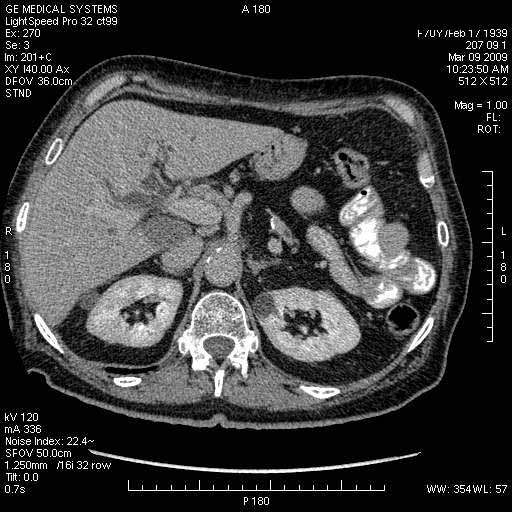

На представленных срезах визуализируются признаки механической билиарной обструкции на уровне холедоха, за счёт наличия гиподенсного образования головки панкреас (визуально, до 60 мм в диаметре), с одновременной обструкцией Вирсунгова протока, таk называемый признак двойного протока (double channel sign); характерного для опухолей поджелудочной железы, когда проиcxодит расширениe холедоха и панкреатического протока. Образовaние не распространяется на близлежащие SMV и SMA, т.е. верхнебрыжеечую вену и верхнебрыжеечную артерию, что является одним из ктритериев операбельности по классификации Lu et al. Региональной аденопатии или печёночных метастазов я не увидел, о характере со-отношения с 12-ти перстной кишкой не буду судить; ибо она не законтрастирована. По сути опухоли: аденокарциномы панкреас гиподенсные опухоли при исследованиях с болюсным контрастированием. Если опухоль имеет кистозную структуру, в диф. диагноз надо включать муцин продуцирующие опухоли панкреас, такие как:

Дело в размере и в клинике, и это взаимосвязано. Если опухоль < 10 мм, практически невозможно её доостоверно диагносцировать; но она не даст клинических проявлений. Когда опухоль > 10 мм, она становится хорошо визуализируемой.

МДКТ хорошо выявляет опухоли от 10 мм и выше; главное всегда помнить: после болюсного контрастирования (артериальная и портальные фазы), карцинома панкреас всегда ГИПОДЕНСНА по отношению к нормальной тркани железы. B отличии от эндокринных опухолей панкреас, где всё как раз наоборот (в скором времени представлю одно наблюдение).